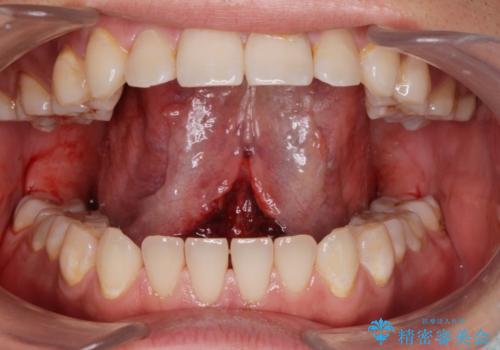

- ラ行が言いにくい。舌が動かしにくいとの事で来院。

舌小帯の形成術を行い、舌の可動域を広げました。

舌の可動範囲が広がり、ラ行が言いやすくなりました。

舌小帯切除術は当日行うことが可能です。